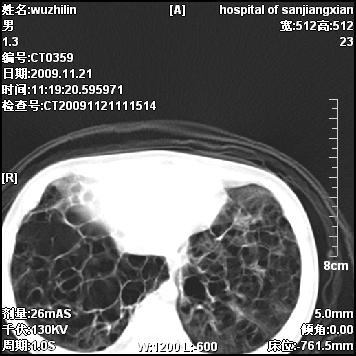

标题: PED3072: 1岁3个月患儿 胸部弥漫性病变 [打印本页]

标题: PED3072: 1岁3个月患儿 胸部弥漫性病变

弥漫性薄壁囊腔,胸膜下及肺底部占优势,双上肺磨玻璃密度影,首先考虑特发性肺间质纤维化,其次囊性肺纤维化,肺淋巴管平滑肌瘤病嗜酸性肉芽肿等;要结合临床综合考虑。

两肺布满多个薄壁含气囊腔,以下肺居多,伴磨玻璃样密度影,左侧气胸。两肺发育不全、两肺多发肺囊肿并感染,其次考虑肺囊腺瘤。